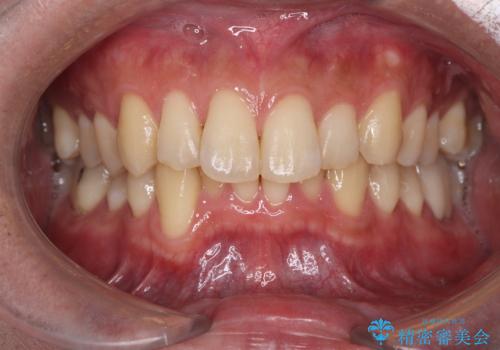

白い歯で清潔感get!初ホワイトニング

- 初めてのオフィスホワイトニングということで痛みなどの不安があったようですが、痛み等なくトーンアップし白くなりました。

ホワイトニングは色味が段々と後戻りしてきてしまうため、定期的に受けていただいたりホームホワイトニングと併用していただくと白さを保つことができます。